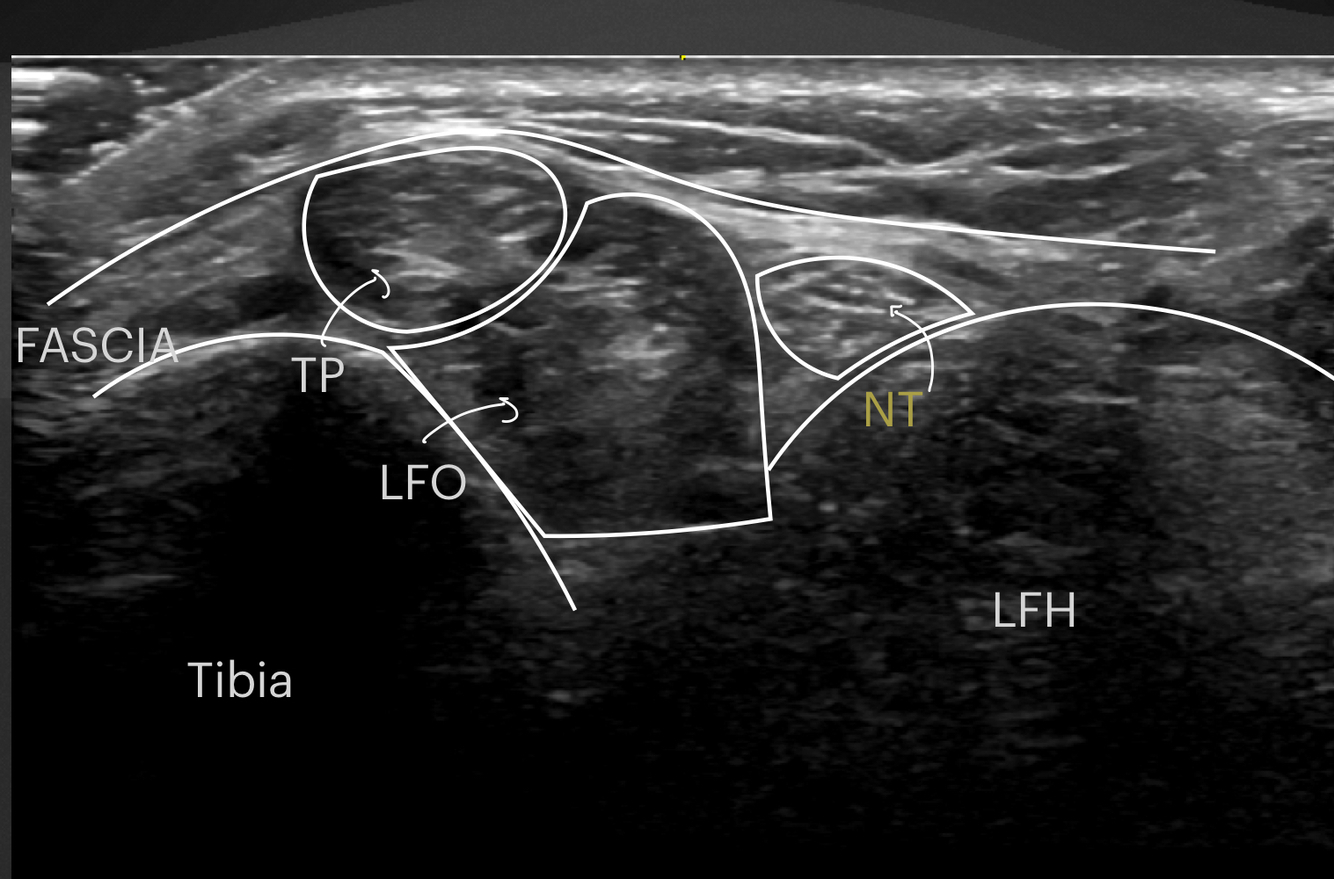

Identifier les structures suivantes

- Tibial post

- LFO

- Nerf tibial